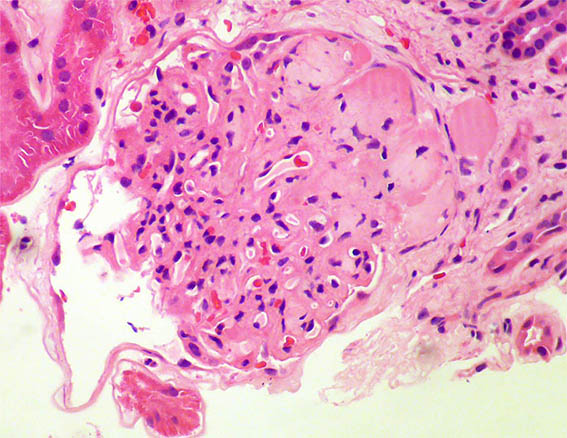

Figure 5. H&E, X400.

Figure 6. H&E, X400.